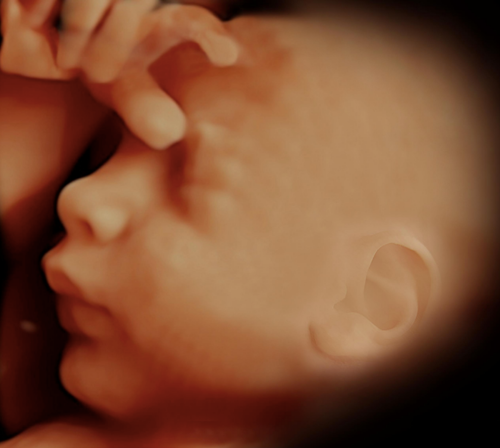

Perfil Biofísico y NST: Monitoreo Esencial del Bienestar Fetal

El Perfil Biofísico (PBF) combinado con el Monitoreo Sin Estrés (NST, por sus siglas en inglés) representa una de las herramientas más completas para evaluar el bienestar fetal durante el embarazo. Este conjunto de pruebas no invasivas permite a los obstetras identificar de manera temprana cualquier signo de compromiso fetal y tomar decisiones oportunas para garantizar la salud del bebé.

La combinación del Perfil Biofísico con el NST proporciona una evaluación integral del estado fetal, evaluando tanto la respuesta cardíaca como la actividad física del bebé, ofreciendo una visión completa de su bienestar intrauterino.